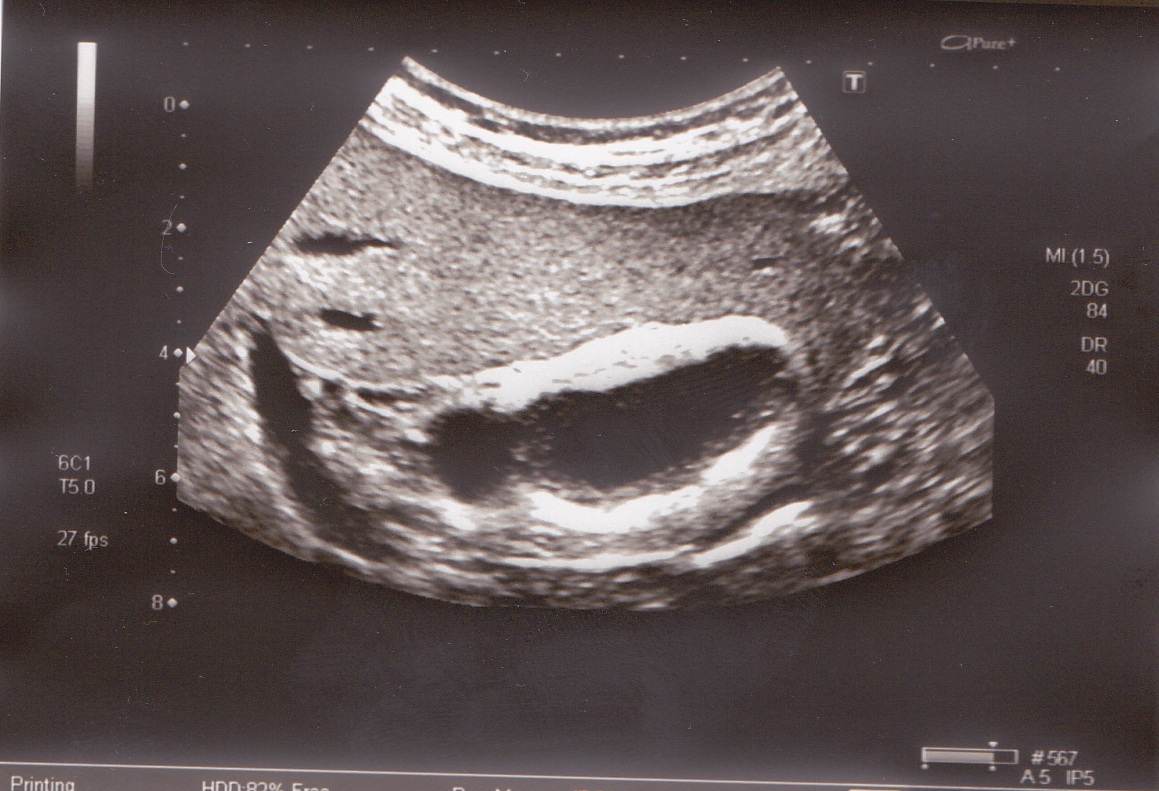

Мужчина, 48 лет, ранее не обследовался. взят на ДУ по поводу СД. направлен на УЗИ. жалоб не предъявляет.

Пациент амбулаторный. Решили с онкологом направить на КТ. Стенка желчного 11мм, в просвете пристеночные несмещаемые гиперэхогенные образования от 2 до 5мм, есть единичные с акустической тенью, однако также несмещаемые. попробую завтра получить снимок более четкий.

вот непонятно,что это и к чему относится. слизистая такая может быть?

желчный в поперечнике.

при ЦДК и ЭД кровоток не регистрируется в области стенки. 2й "слой" охватывает пузырь внутри циркулярно. содержимое анэхогенное, при перемене положения тела- на боку,на животе,сидя,стоя,лежа на спине- ничего никуда не перемещается.